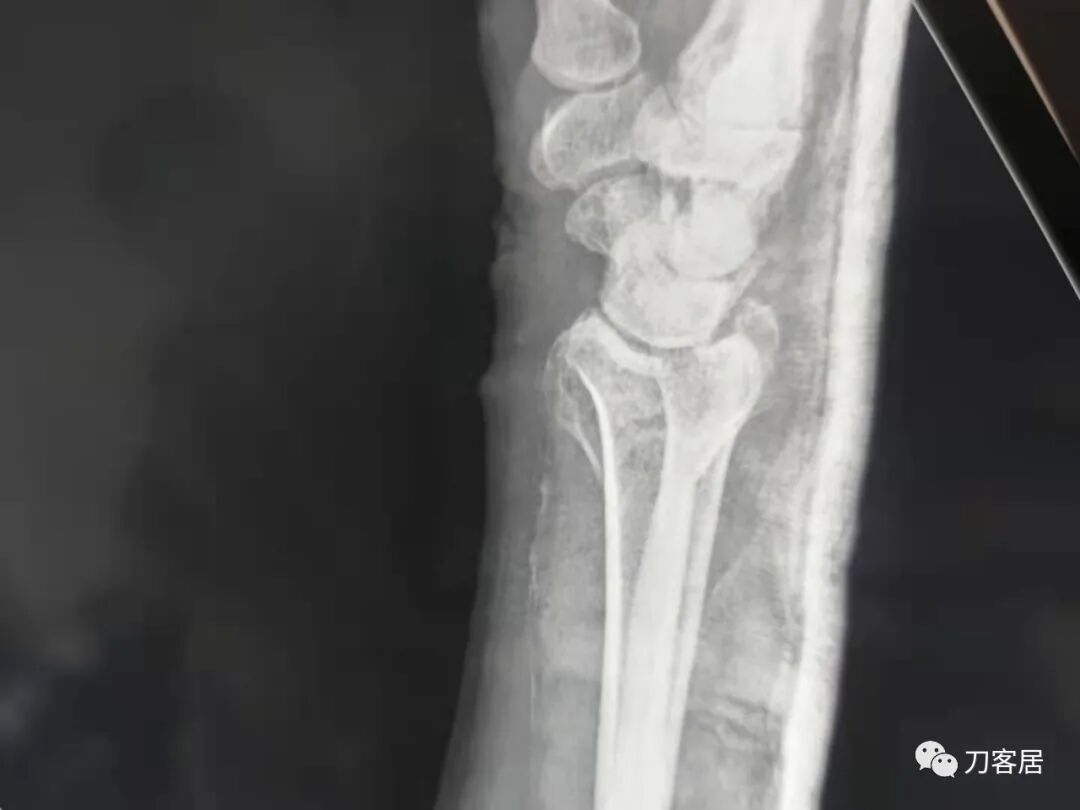

下面是这个6岁孩子,尺桡骨远端双骨折的术前及术后片子和外观照片。

1.  这是一个很简单的6岁儿童无移位的尺桡骨远端骨折。没有皮肤损伤,没有移位,没有骨折碎块儿。

2.  这个骨折处理起来也很简单,单纯的打石膏托或者中医的小夹板,或者正规的包括腕关节和肘关节的管型石膏外固定4周即可治愈该骨折。实在不行,如果这个孩子比较听话,不太调皮的话,用一本书,一个三角巾悬吊固定4周,都可以治愈该骨折。但是给这个患者用外固定架做了手术,而且桡骨远端的几颗克氏针距离骨折线太近,其中一枚克氏针进入到骨折间隙内。从这个术中图片来看,术者的外固定手术技术也有待于进一步的提高。毕竟术者应该还很年轻。从X线片来看,前臂及手的尺侧有不透光影,应该还使用了外固定石膏绷带托,而且我猜测应该是高分子的石膏绷带托,这个是纯属猜测,不一定是对的,不过如何解释前臂尺侧的不透光影呢?如果真是用了石膏绷带外固定的话,那为啥要做手术呢?外固定架术后就不该再用石膏绷带托辅助了。